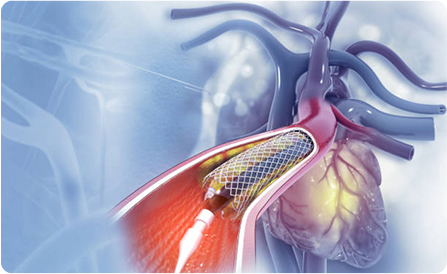

Interventional Procedures

Expert in angioplasty, stenting, and minimally invasive procedures to restore heart function effectively and improve patient recovery outcomes.

- Interventional Cardiology: Coronary angiogram, coronary angioplasty, minimally invasive cardiac bypass.

Interventional cardiology uses minimally invasive procedures like angioplasty and stenting to treat blocked arteries, restore blood flow, and prevent heart attacks. It offers faster recovery, less pain, and avoids the risks of open-heart surgery.